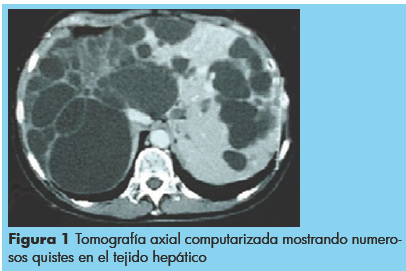

Un hombre de 50 años con una tumoración abdominal localizada en el hipocondrio y el flanco derecho, asociado con una sensación de llenura, digestión pobre, acidez y constipación. El dolor se intensificó en el curso del último mes irradiando a la región lumbar derecha. No presentaba síntomas de ictericia. Exámenes de laboratorio evaluando función hepática presentaron resultados normales y análisis de suero para hidatidosis fueron negativos. Una tomografía axial computarizada abdominal de mostró hepatomegalia de configuración lobulada con densidad alterada debido a numerosas figuras anecoicas de distintos tamaños con paredes delgadas sin absorción de medio de contraste, predominantemente en el lóbulo derecho, sin dilatación de los conductos hepáticos pero comprimiendo el estómago (Figura 1), y asociado con una imagen quística del bazo (Figura 2).